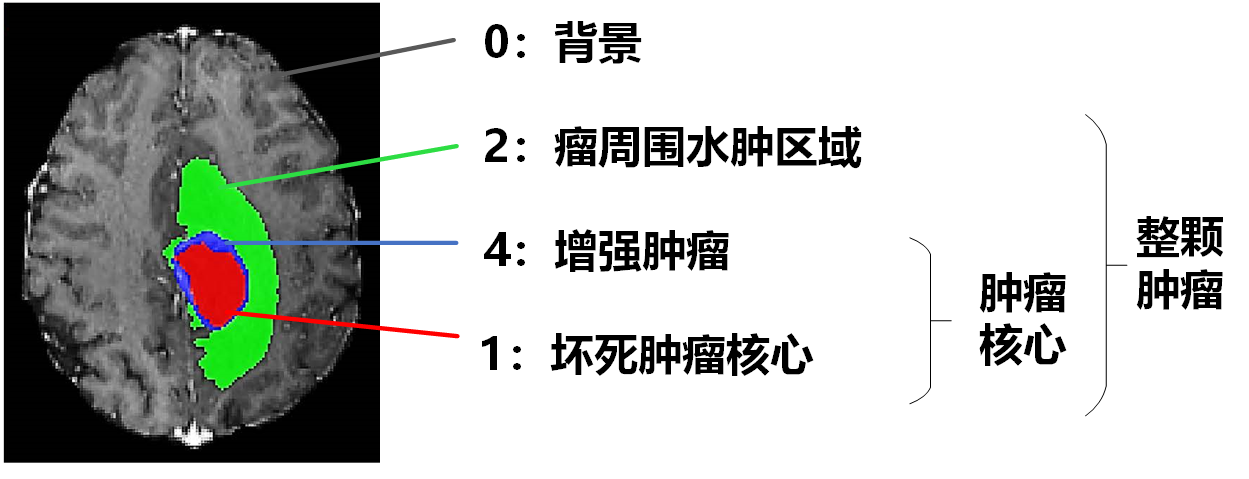

三、标签描述

label 0:背景(background)

label 1:坏死肿瘤核心(necrotic tumor core,NCR)

label 2:瘤周围水肿区域(peritumoral edema,ED)

label 4:增强肿瘤(enhancing tumor,ET)

比赛要求按区域进行分割,最终需识别出三个子区域:整颗肿瘤(包括label1、2、4)、肿瘤核心(包括label1、4)以及增强肿瘤(只包括label4)